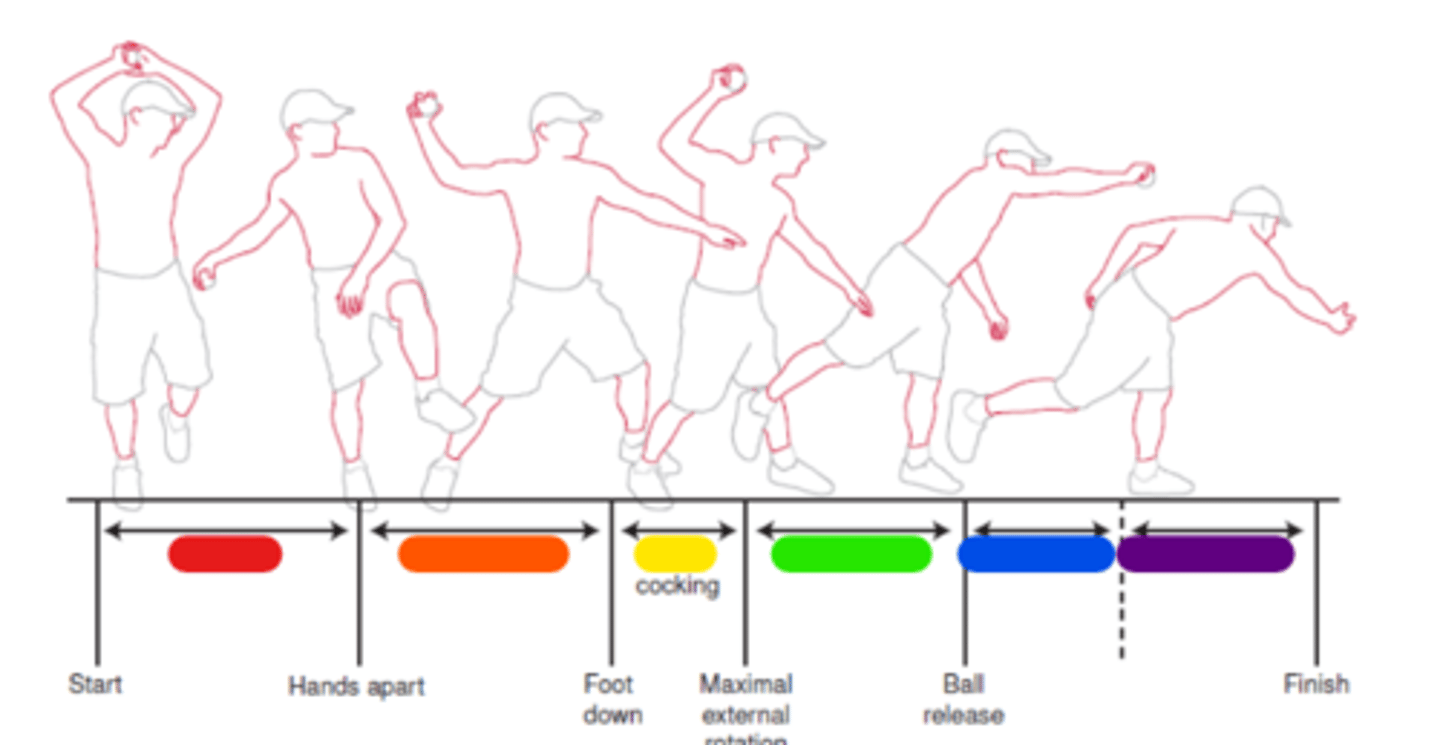

Windup

Red in image.

Early cocking

Orange in image.

Late cocking

Yellow in image.

Acceleration

Green in image.

Deceleration

Blue in image.

Follow through

Purple in image.